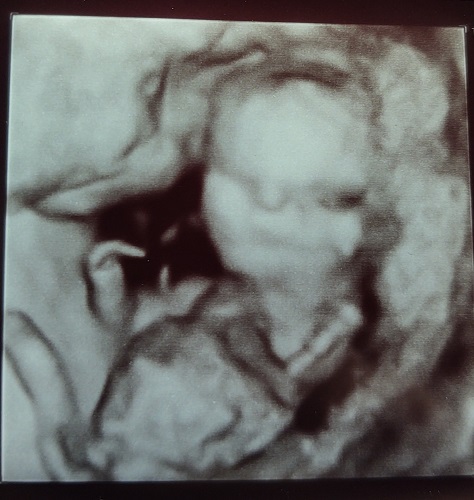

Regular ultrasounds are cool enough. We tried to get a 3-D shot of Ella, but she kept putting her hands in front of her face. We never really got a full face shot of her. Check out what we saw today…

It’s a little blurry, but there is the baby, looking right at us! WOW!